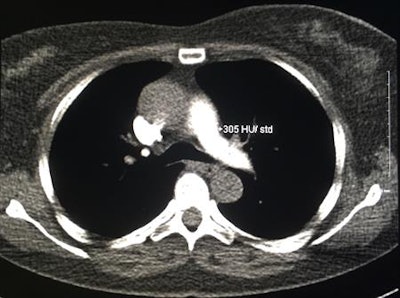

Above: Axial CT image of the midthorax from a CTPA monitoring scan (bolus-tracking 80-kV technique). The region of interest is centered over the pulmonary trunk and measures 305 Hounsfield units, which is sufficiently high to trigger the diagnostic scan. Below: A scout topogram from the same CTPA study. The transverse line illustrates the level at which the monitoring scan was performed and demonstrates that repeated scanning at this level would increase breast organ dose. All images courtesy of Dr. David P. Mitchell."Contrast-monitoring techniques are often considered to be minor, if not negligible, contributors to radiation dose, but, in fact, the monitoring scan has a disproportionate effect on breast dose due to its repeated imaging directly over the breasts and the tendency of monitoring scans to be repeated," Mitchell wrote in an email to AuntMinnieEurope.com. "The protocol optimizations required enact significant dose reductions that can be carried out in any radiology department, without compromising diagnostic CTPA quality."

"In practice, the contrast-monitoring component entails the continuous imaging of the pulmonary trunk after contrast injection has begun, which can either trigger the diagnostic scan at a predetermined Hounsfield level (i.e., bolus tracking) or can be used to accurately time a separate diagnostic study (i.e., test-bolus timing)," they wrote.